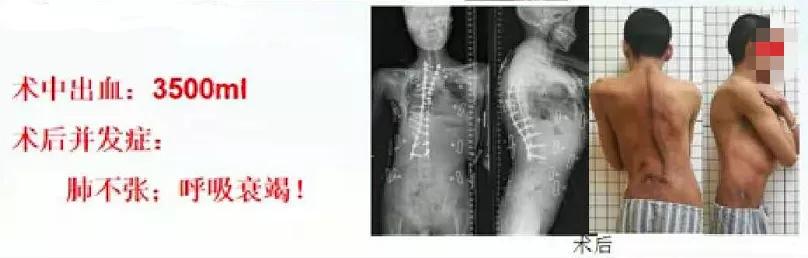

患者男,27岁,诊断:重度特发性脊柱侧后凸,头盆环牵引术后。术前侧凸Cobb角120°,后凸Cobb角143°,顶椎T8/9,行头盆环牵引11个多月。2018年行T1-L4椎弓根螺钉+胸廓成型+T8/9经间盘截骨矫形内固定术。